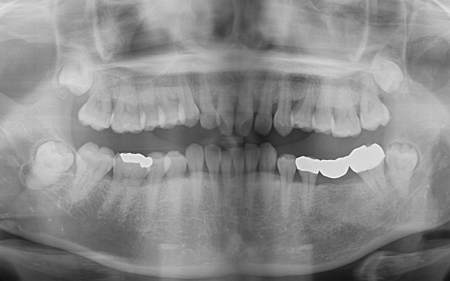

加えてレントゲン検査では、上前歯を中心に歯を支える骨が減少していることも確認できました。

これらの検査結果から、お口全体に中等度から重度の歯周病があると考えられました。

特に、外れてしまったブリッジの土台となっている手前の歯は、歯周病の影響で揺れていました。

さらに奥の歯には8ミリほどの深い歯周ポケットも認められました。